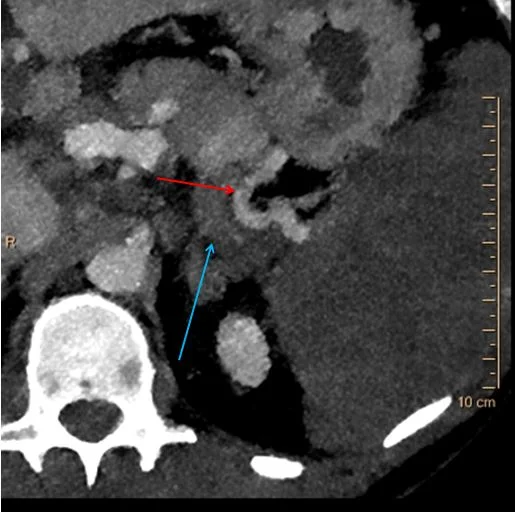

40 keV image: Splenic artery is patent to the hilum (red arrow). The splenic vein appears thrombosed (blue arrow). Note the spleen is very hypodense on the low keV image, consistent with absent iodine uptake.